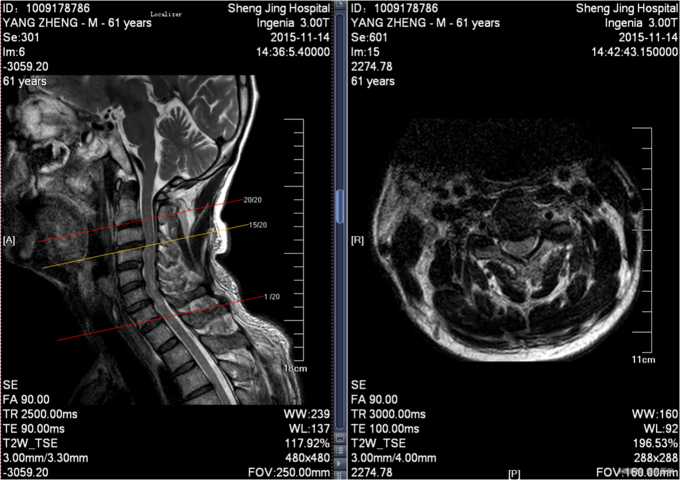

患者于2015年11月13日15:30左右因在工厂2米高管道上作业不慎坠落致颈部疼痛,四肢活动受限,受伤后被家人送入当地北台镇医院,输一袋葡萄糖液,转入本溪二院,行口腔科、眼科缝合行X线检查,头颅ct检查。患者及家属为求系统治疗,急来我院,急诊予以行辅助检查,提示:颈4-6棘突骨折,颅骨多发骨折;急诊以“颈椎外伤”为主诊断收入我科。病来患者一般状态无头晕及头痛,,无恶心及呕吐 ,留置导尿中。

前额部敷料包扎中,打开敷料见右眉处7cm大小创口已缝合,无渗出,前额处可见一5cm大小创口已缝合,颈领保护中,触痛。双手感觉减退。患者平乳头以下触觉存在,痛觉及运动消失。屈肘肌力(R4,L4),伸肘肌力(R0,L0),手掌掌屈肌力(R0,L0),手掌背伸肌力(R0,L0)。双手握力(R0,L0)。髂腰肌肌力(L0级,R0级),伸膝力(L0级,R0级),足背伸力(L0级,R0级),足跖屈肌力(L0级,R0级),神经反射:BCR:L(-)R(-),TCR:L(-)R(-),肱桡肌反射:(-)R(-),PSR: L(-)R(-),ASR: L(-)R(-),Hoffmann Sign:L(-)R(-), Babinski Sign L(-)R(-) 双侧桡动脉、足背动脉可扪及搏动,末梢血运良好。

患者入院后完善相关检查,明确诊断,手术指征明确,于2015-11-17日于全麻下行颈椎后路单开门椎板减压,侧块螺钉内固定术,术后经抗炎、止疼等对症治疗后,患者恢复顺利,切口愈合良好,今日可出院。